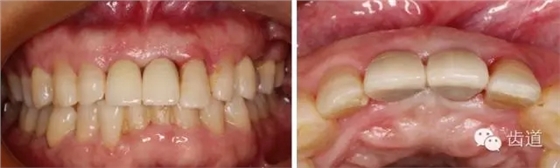

初診照片(正面照)

初診照片(合面照)